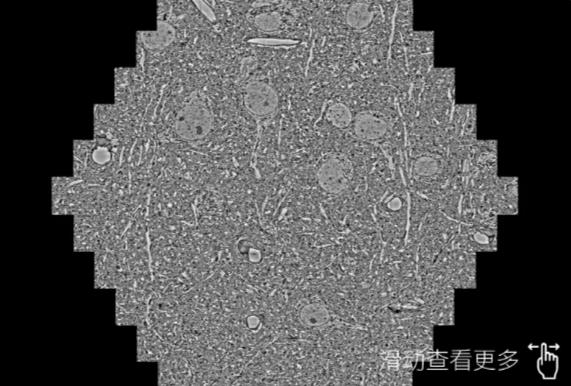

鼠脑切片。左图使用商洛蔡司商洛扫描电镜MultiSEM706对165μmx143pm面积区域成像,耗时仅需1.5秒。右图为鼠脑切片中30μm区域放大效果。样品由芝加哥大学B.Kasthuri提供。

使用蔡司高速商洛扫描电镜MultiSEM对1mm²人脑皮层组织进行高分辨成像,并对其中的各种细胞结构进行三维重构分析。左图展示了2x3mm²组织平面中锥体神经元的三维重构效果。右图显示了局部体积神经元三维重构。图像由哈佛大学chtman实验室提供,渲染图由D. Berger 制作。